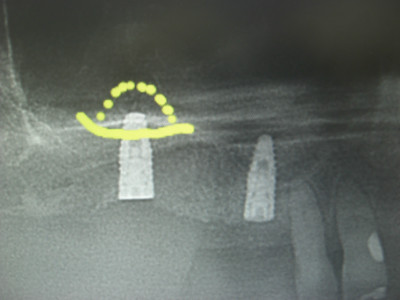

5/28日施術分オペ画像

この画像も5月28日施術分のオペ画像になります。

この症例は右上3番が歯根破折の為に保存不可能な状態になり尚且つ入れ歯の鉤歯であったが為に、入れ歯の保持が厳しくなり来院された患者様でした、。

すでに下顎には複数本のインプラントを埋入され快調にご使用されているとのことで、上顎にもインプラントによる義歯固定の治療を希望されましたので3番相当部は抜歯即時で埋入し6番相当部にはソケットリフト法を併用しましてインプラントを問題なく埋入いたしました。